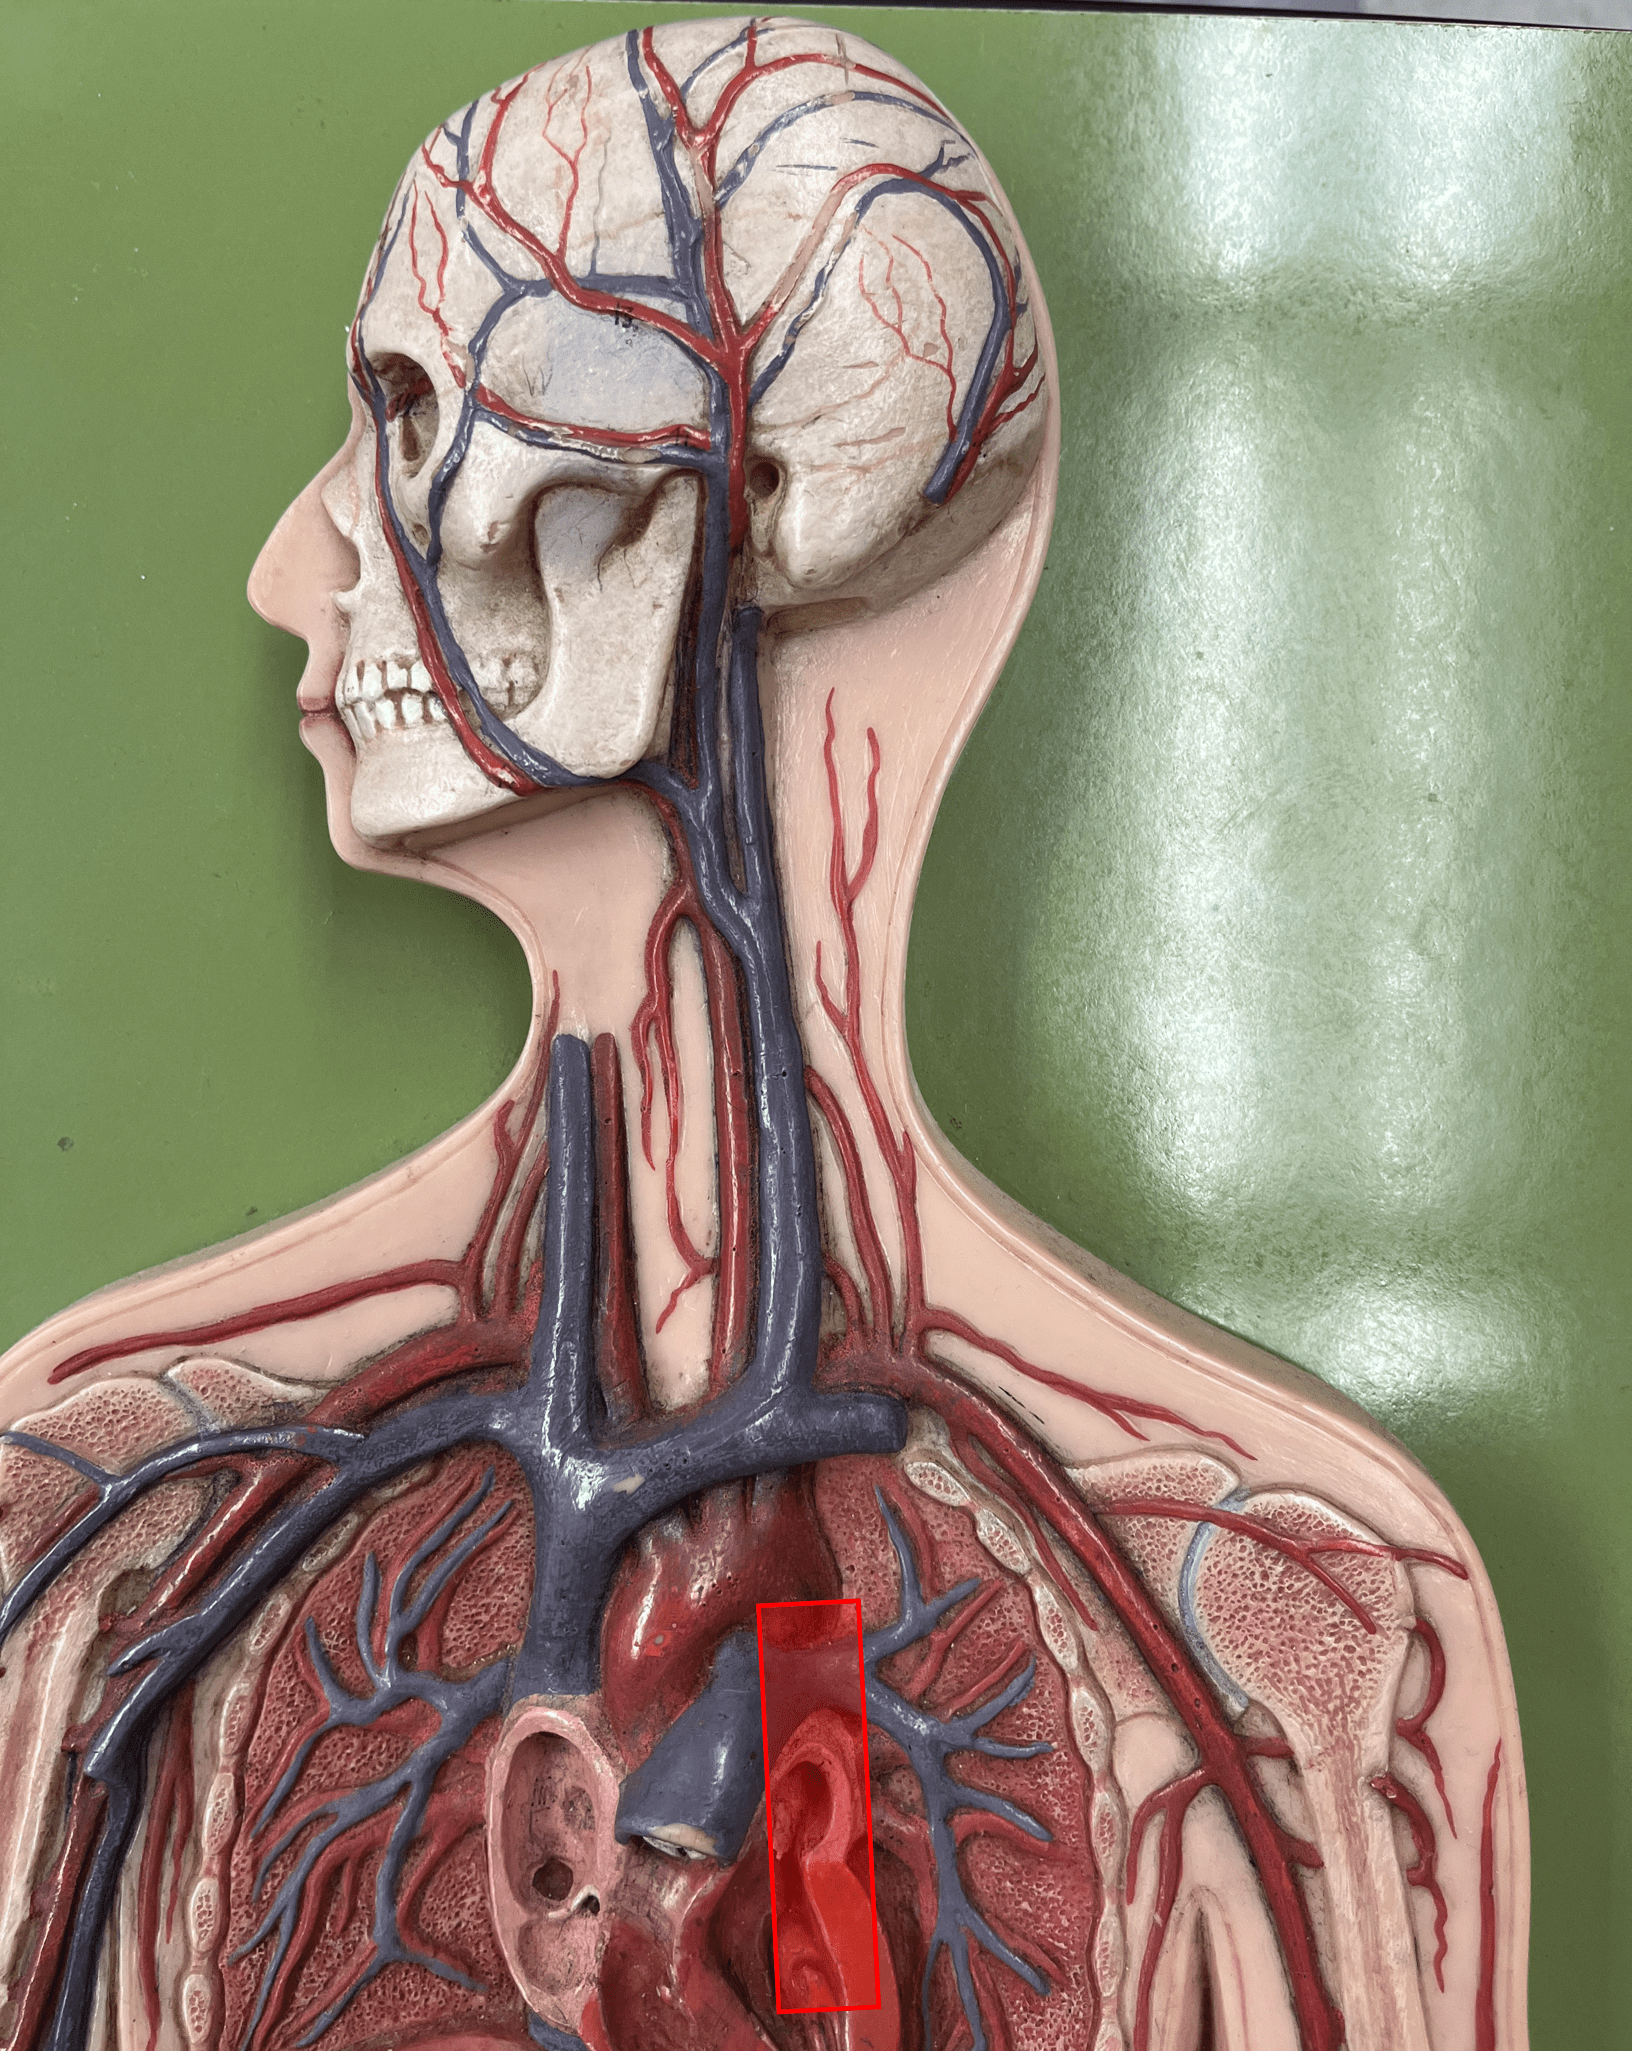

ascending aorta

• An artery of the thorax.

• Originates from the left ventricle of the heart.

• Supplies its branches.

• Originates from the left ventricle of the heart.

• Supplies its branches.

aortic arch

• An artery of the thorax.

• Originates as the continuation of the ascending aorta.

• Supplies its branches: the brachiocephalic trunk, L. subclavian artery, and L. common carotid artery.

• Originates as the continuation of the ascending aorta.

• Supplies its branches: the brachiocephalic trunk, L. subclavian artery, and L. common carotid artery.

brachiocephalic trunk

• An artery of the thorax.

• Originates from the aortic arch.

• Supplies its branches: the R. subclavian and R. common carotid arteries.

• Originates from the aortic arch.

• Supplies its branches: the R. subclavian and R. common carotid arteries.

subclavian artery

• An artery of the thorax.

• Originates from the brachiocephalic trunk (R.) or the aortic arch (L.).

• Supplies its branches.

• Originates from the brachiocephalic trunk (R.) or the aortic arch (L.).

• Supplies its branches.

superior vena cava

• A vein of the thorax.

• Drains the azygos and brachiocephalic veins.

• Empties into the right atrium.

• Drains the azygos and brachiocephalic veins.

• Empties into the right atrium.

brachiocephalic vein

• A vein of the thorax.

• Drains the subclavian, external jugular, vertebral, internal jugular, and left intercostal (1-3) veins.

• Empties into the superior vena cava.

• Drains the subclavian, external jugular, vertebral, internal jugular, and left intercostal (1-3) veins.

• Empties into the superior vena cava.

subclavian vein

• A vein of the thorax.

• Drains the axillary vein.

• Empties into the brachiocephalic vein.

• Drains the axillary vein.

• Empties into the brachiocephalic vein.